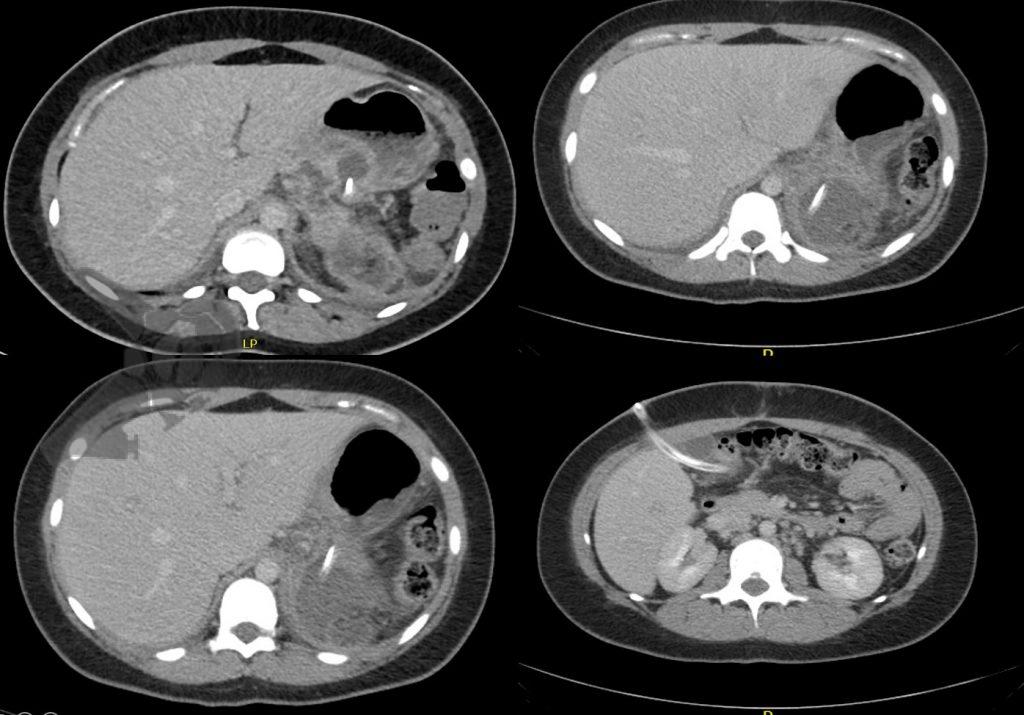

- TC de abdomen revela colección retrogástrica en contacto con el margen de resección del páncreas (Figuras 1 y 2).